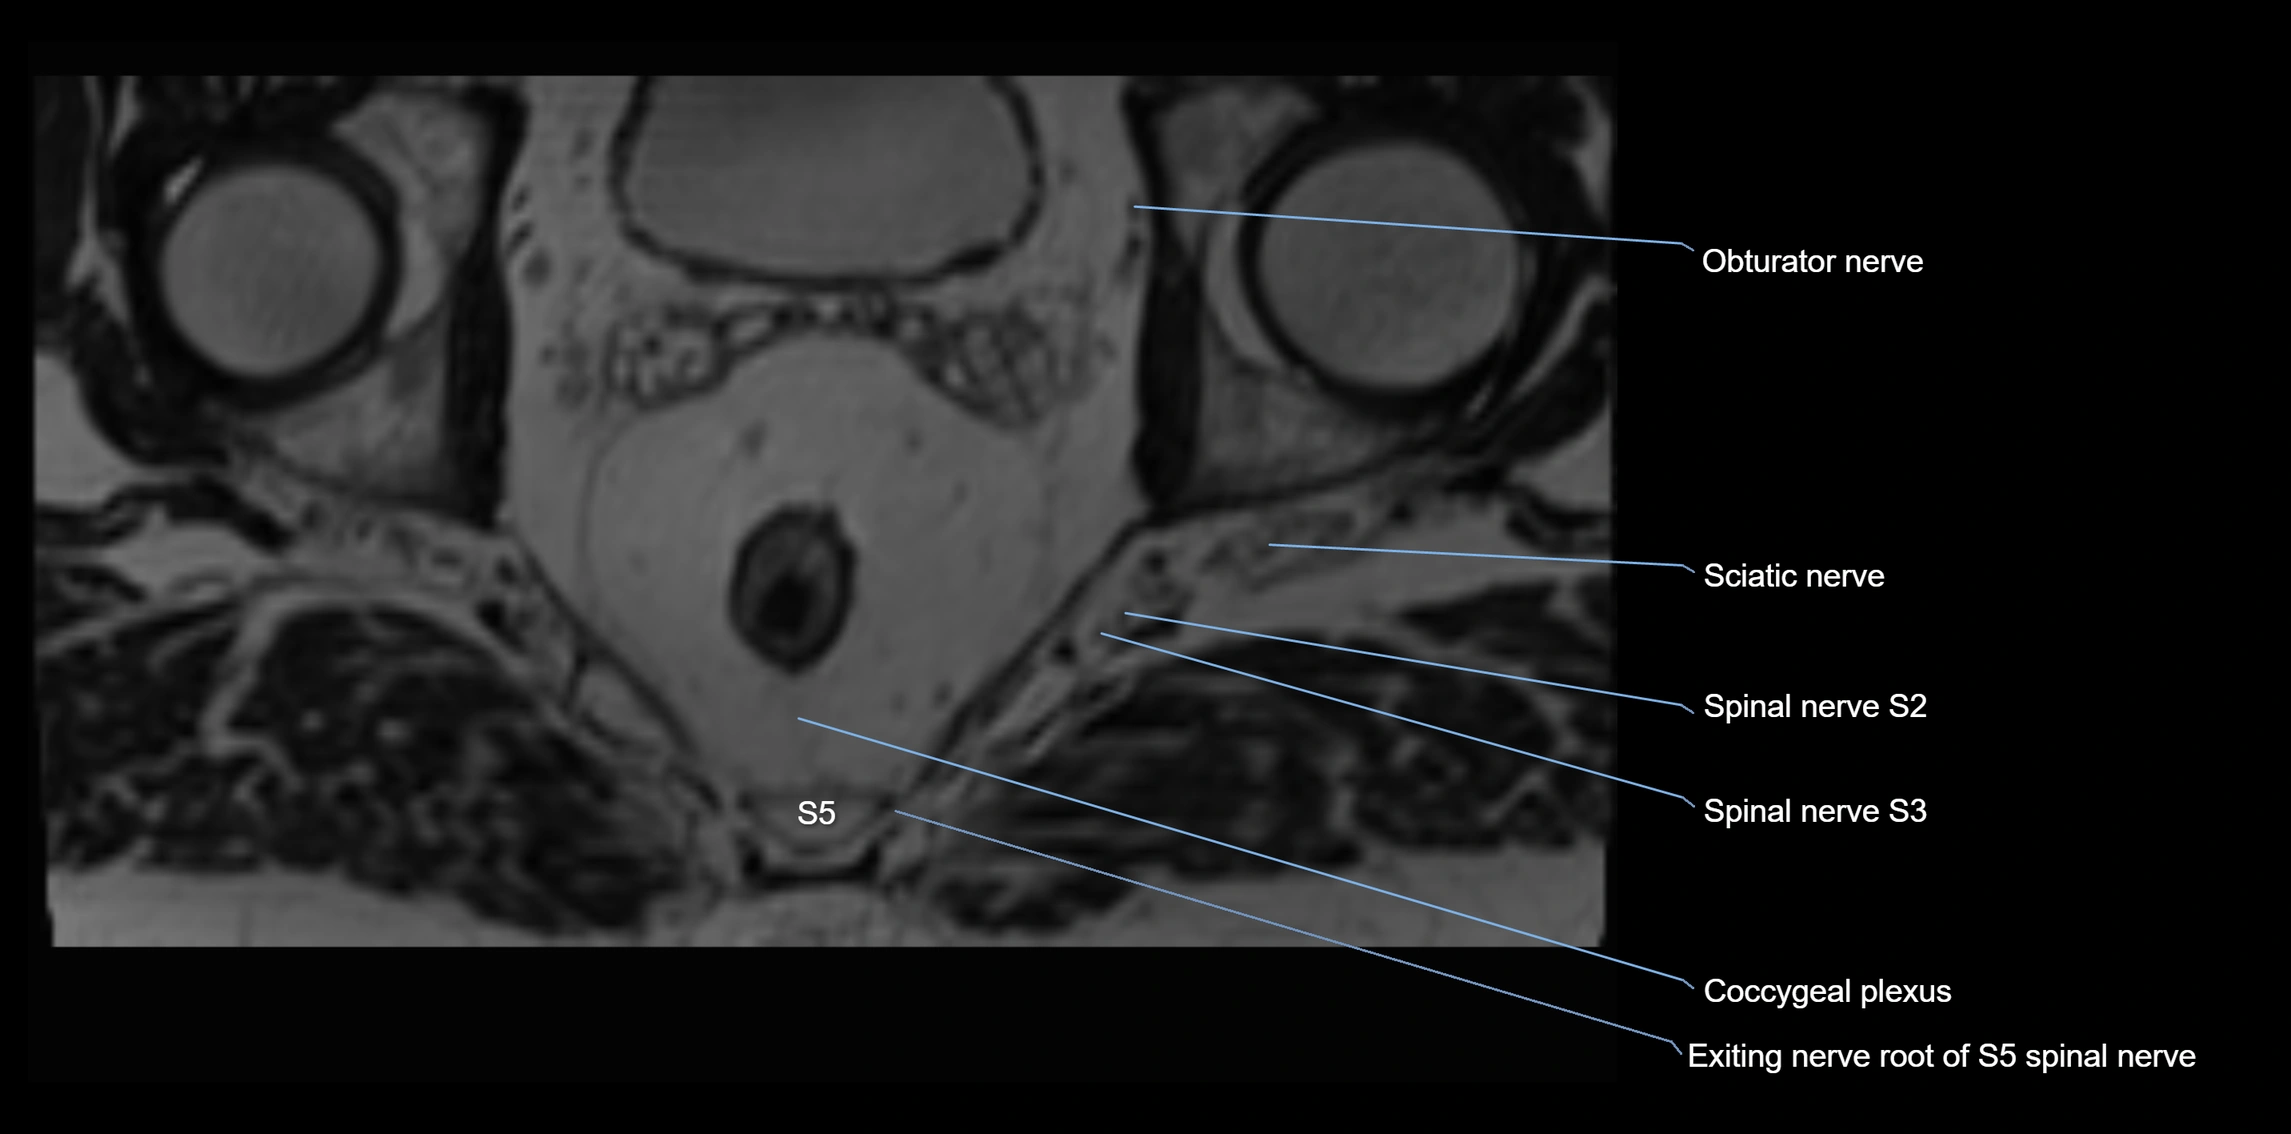

MRI Appearance

T1-weighted images:

• Nerve appears as a very thin low-to-intermediate signal intensity structure

• Surrounded by bright fat, aiding visualization

T2-weighted images:

• Nerve shows intermediate to mildly hyperintense signal compared to muscle

• Pathological involvement appears brighter

STIR (Short Tau Inversion Recovery):

• Normal nerve appears dark

• Inflamed or entrapped nerve appears bright hyperintense

T1 Fat-Sat Post-Contrast:

• Normal nerve enhances minimally

• Pathologic nerve (neuritis, entrapment, tumor infiltration) shows focal or diffuse enhancement

3D T2 SPACE / CISS:

• Nerve appears intermediate to mildly hyperintense compared to muscle

• Surrounded by bright fat or CSF, improving visualization

• Best sequence for mapping small pelvic nerves such as the anococcygeal

MRI image

image